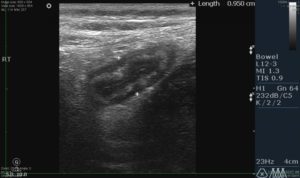

Диагностика

Диагностика заболевания обычно не представляет сложностей и может потребовать наблюдения за пациентом в течение примерно трех часов. Для отличия аппендицита от других заболеваний желудочно-кишечного тракта может потребоваться дифференциальный анализ. В некоторых случаях может потребоваться диагностическая лапароскопия. Стандартные методы диагностики гнойного аппендицита включают:

• ректальное обследование;

• общий анализ крови;

• ультразвуковое исследование;

• рентгенография;

• электрокардиография.